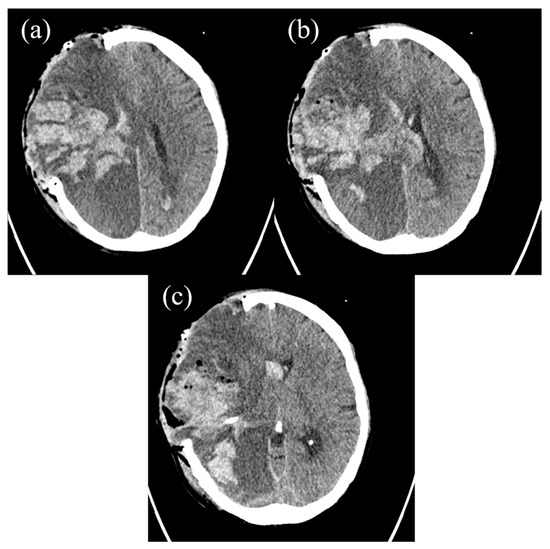

2. The Case Report